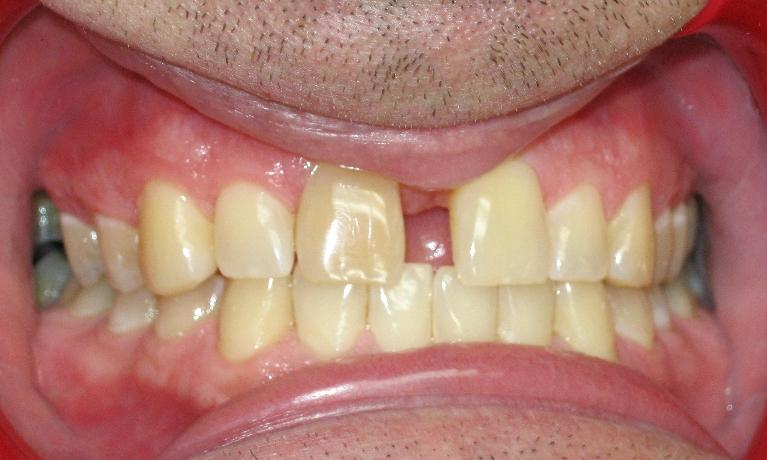

When people have chipped or worn teeth, it can result in esthetic concerns as well as produce discomfort of the teeth or joints. While patients want things fixed quickly, our first challenge is to determine the cause of the problem.  We always want to know the cause because we want to prevent further breakdown of the teeth, as well as have long term success with any new restorations we may place.  Sometimes the fix can be as simple as a filling, a crown or a veneer,  while other times the optimal treatment may get more involved. We often see an underlying cause of tooth breakdown related to grinding or clenching teeth. When there is significant wear throughout, the restorative treatment to address this problem may involve a full rehabilitation of crowns on many, or even all teeth to re establish a normal alignment of the teeth.  Other times we see an underlying cause that is orthodontic in nature and we need to treat the patient with orthodontics such as braces or Invisalign prior to any restorations.  So, our “cosmetic” options will be determined by the problems we are presented with, and we will always show our patients X-rays, photos, and plaster models to explain our findings and recommendations prior to starting any treatment. If you have any concerns with chipping or wear, give us a call so we can see what options you may have to restore your optimal smile.